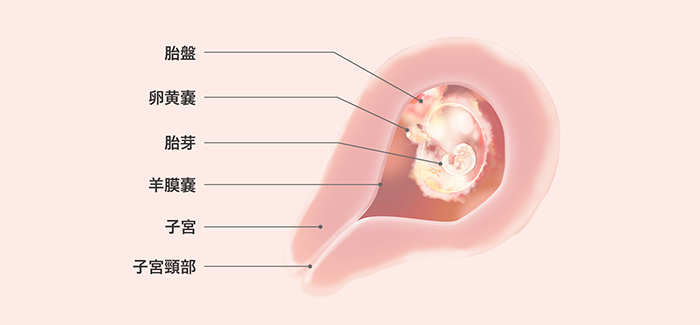

妊娠はどのように成立するのでしょうか 妊娠4週目 タカキ薬局 愛知県岡崎市の不妊症 子宝相談

医師監修 妊娠4週はどんな時期 初期症状と赤ちゃんの状態 起こりうるリスク マイナビウーマン子育て

医療監修 妊娠2ヶ月目の妊婦と胎児の基礎知識 心拍確認の時期と生活での注意点 ママリ

妊娠2ヶ月 妊娠4週 5週 6週 7週 妊娠初期 のおなかの赤ちゃんの様子 妊娠 出産 育児に関する総合情報サイト ベビカム

妊娠2か月目 妊娠4 7週の胎児の様子 母体の症状や気を付けること 妊娠初期 All About

妊娠4週目の特徴と赤ちゃんの変化は 妊婦専用のマタニティマッサージ治療院 キコニア